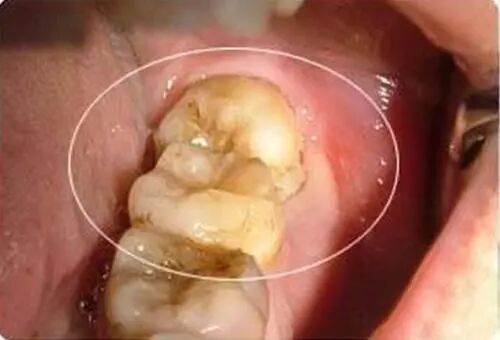

蛀牙到牙髓为啥不能杀牙髓?

有些患者因为出现了蛀牙,吃东西时就不能“冷热酸甜,想吃就吃”,这时候患者的愿望就是医生把洞补起来后一了百了。

但是很多情况下龋齿已经危及牙髓,简单的修复治疗可能无法消除牙髓炎症,反而会增加日后治疗的难度。